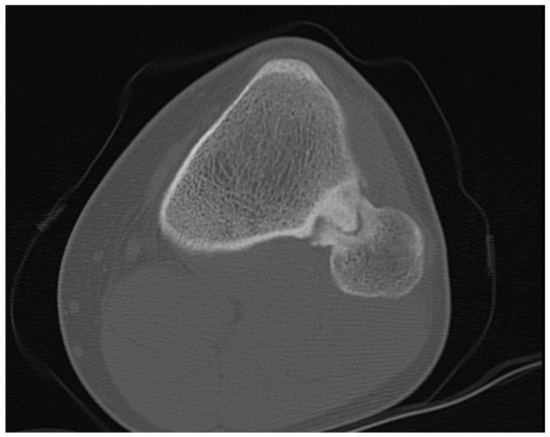

The CT scan without contrast of the knees showed partial sclerosis of the protuberance, and the continuity with the medullary cavity was present (Figure 2).

Figure 2. CT scan in horizontal view showing the synostosis of the left side.